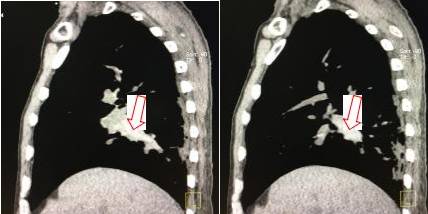

纵隔窗:

冠状位及矢状位重建示右肺动脉干及上下肺动脉分支内均见高密度影(红箭示) 医学百科网 | YxBaike.Com